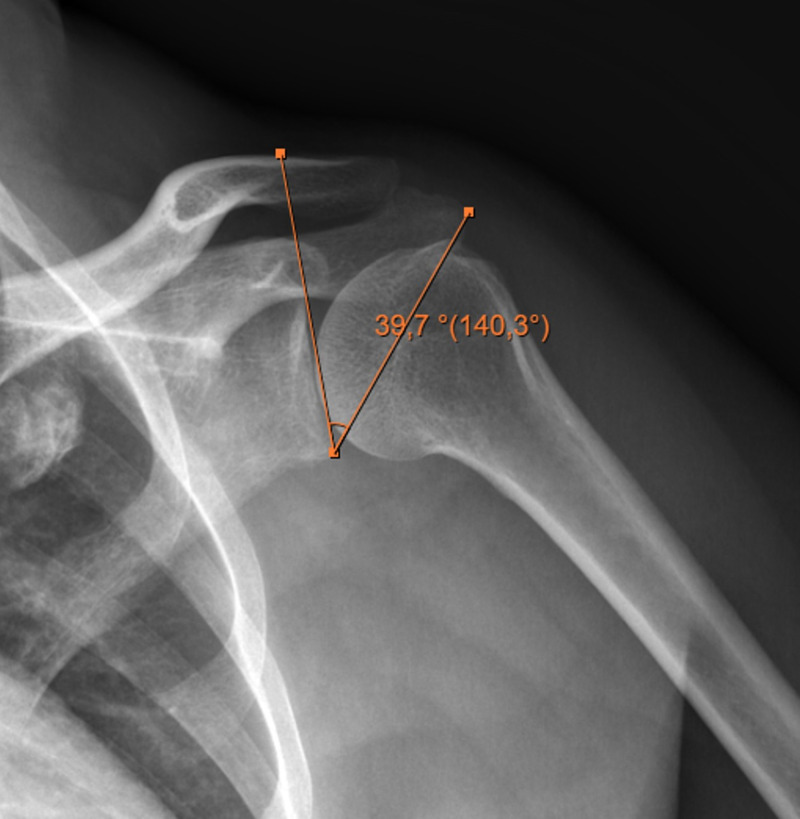

Methods: Ninety-two patients (33 male, 59 female; mean age: 47 ± 9.7) with calcific tendonitis were included in this retrospective study. Critical shoulder angle (CSA), slope angle, lateral acromial angle (LAA), acromion index (AI), acromial type according to Bigliani, and the morphology of the calcific deposits according to Gartner and Heyer were assessed on x-rays. The localization and volume of the calcific deposits were assessed using magnetic resonance imaging (MRI). Patients were divided into 2 groups: CSA < 33° (group 1) and CSA ≥ 33° (group 2).

Results: The median CSA was 33.5° (range=23°-51°), lateral acromial angle (LAA) was 83.6° (range=60°-106°), acromial index (AI) was 0.7 (range=0.4-0.9), and slope angle was 24.1° (range=3°-40°). Lateral acromial angle (P=.000) and AI (P=.000) were statistically different between the 2 groups. Critical shoulder angle was correlated with LAA (P=.000) and AI (P=.000); deposit volumes were correlated with slope angle (P=.001), Bigliani type of the acromion (P=.009), and deposit stage according to Gartner and Heyer (P=.004). There was a correlation between deposit localization and its volume; the size of the deposit increased anteriorly (P=.000).